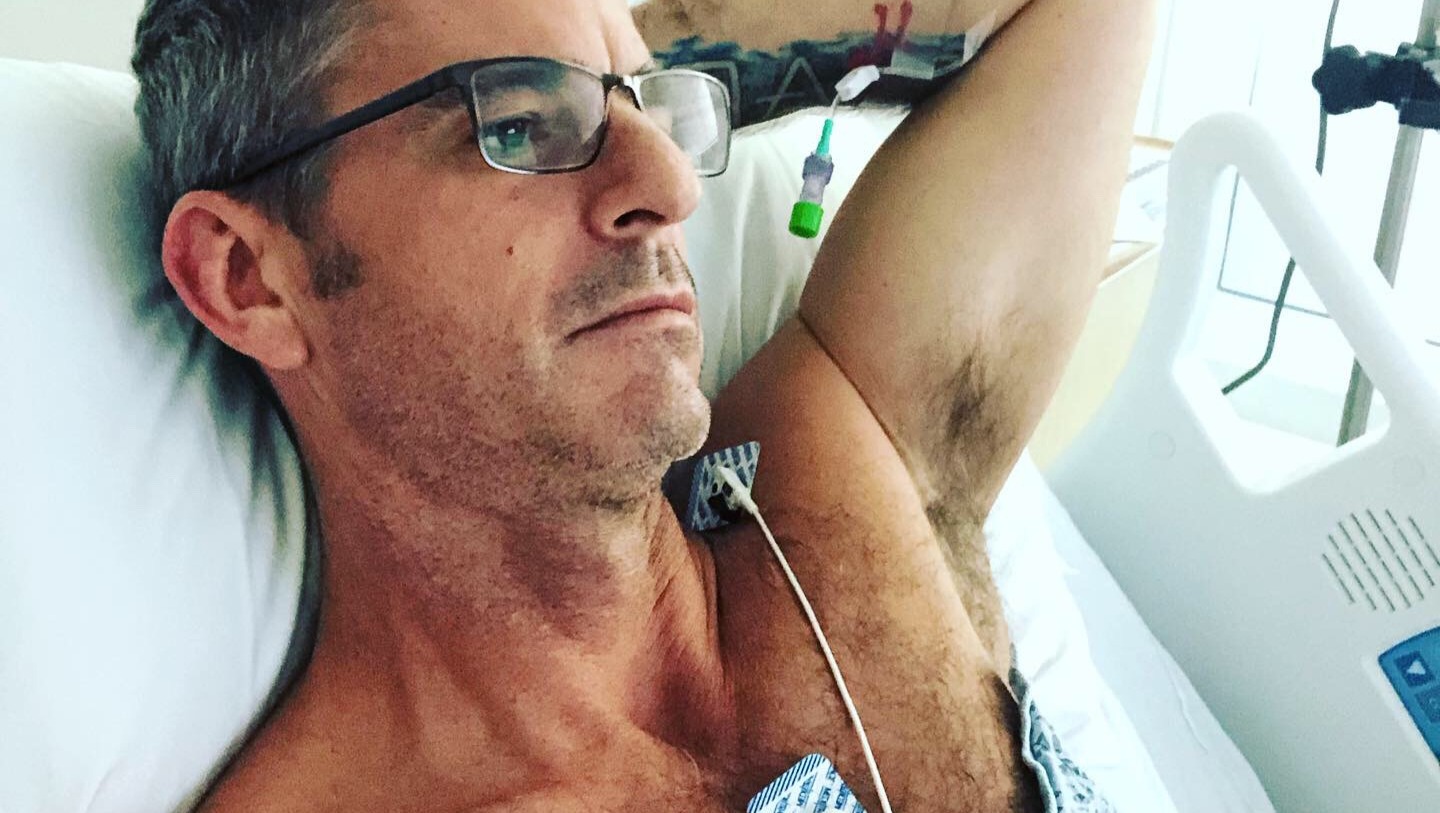

"In August 2019, I contracted a virus while on a quick trip to the bay area. I didn't think much of it at the time, but slowly my health continued to deteriorate. I had a lingering cough, started to feel more run down, shortness of breath. It came to a head on September 29th, 2019. I went to the emergency room and before I could say anything to the nurse behind the desk, they called code blue and I was immediately put on a gurney and rushed into a room surrounded by numerous doctors and nurses.

I had a blood clot in my left atrium, my heart swelled to twice its normal size and my lungs were approximately 70% filled with fluid.

Ejection Fraction(EF) is the heart's ability to pump blood efficiently. An average EF is 55-70 and mine had dropped to 11.

With medications, I've been trying to manage my Afib (abnormal heart beat) and get my heart back to normal. My EF started to climb, but the Afib persisted. In July 2021, I received news that my heart walls are deteriorating and my EF has dropped to 20 and the doctors warned me I needed an implant defibrillator to save me from a possible massive heart attack.

I had the procedure done November 30th, 2021 and my doctor put me on disability for the foreseeable future.